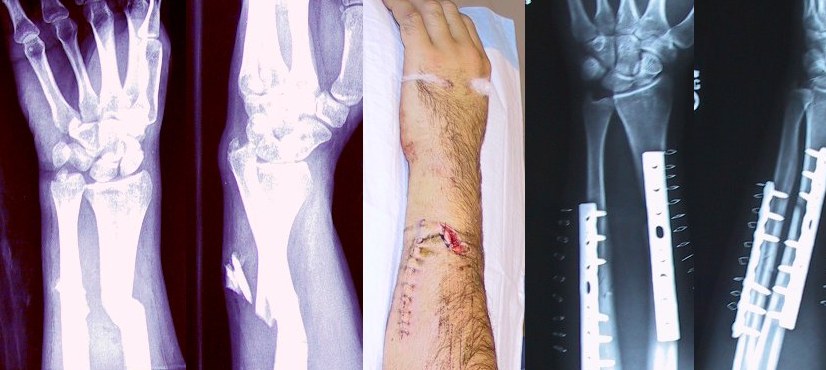

開放性による骨折の分類

・開放性骨折

・閉鎖性骨折(非開放性骨折)

開放性骨折とは、骨が飛び出してしまっている状態の骨折です。

この場合は出血量も多く、細菌感染の可能性もあり緊急手術の適応となります。

骨折はレントゲン診断ではっきりわかりますので、判別が難しい場合はレントゲン診断が必要になります。

骨折の治療方法

骨折の治療方法としては、安静にします。

安静にする際に、しっかり固定して骨がくっつきやすい状態を作ることが重要です。

その為に、骨折の場合はギブスなどで固定します。

また、骨折で位置がずれてしまっている場合は手術でボルトなどを用いて固定することもあります。

どちらにしろ、骨折の場合は安静・固定が必要です。